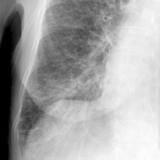

APE 1

Date: 11/05/2005

Views: 4072